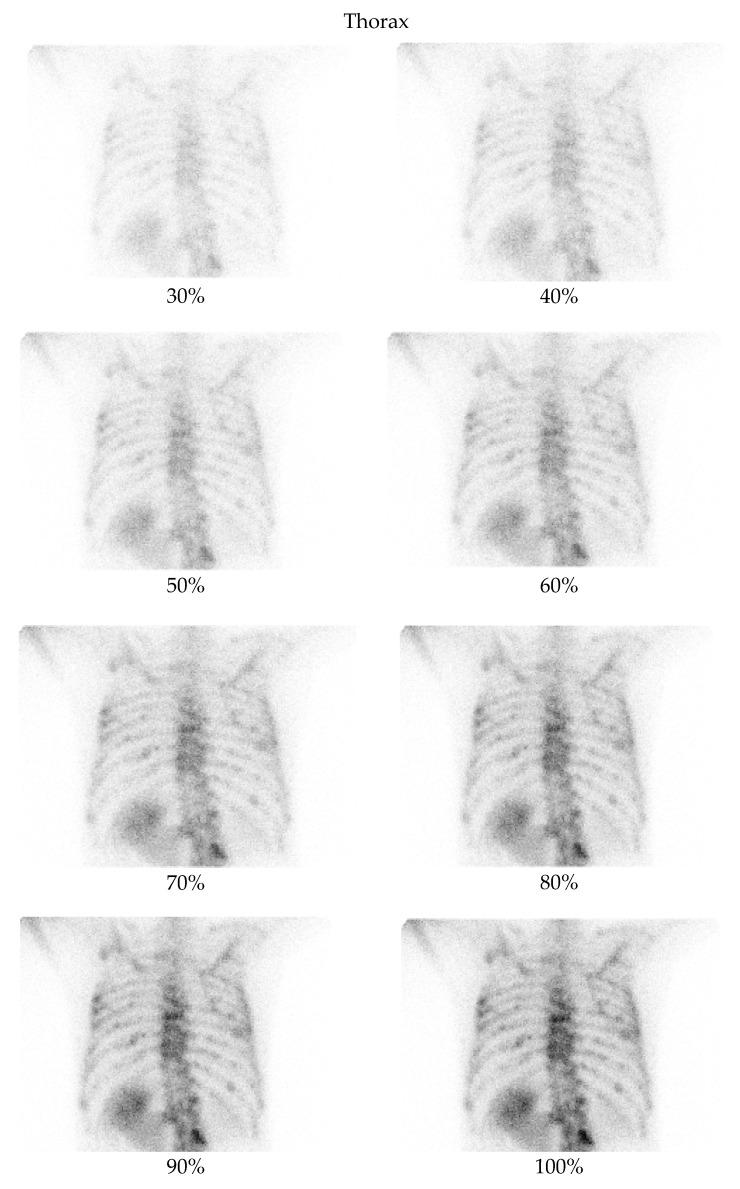

This study proposes a novel deep learning approach for enhancing low-dose bone scintigraphy images using an Enhanced Convolutional Autoencoder (ECAE), aiming to reduce patient radiation exposure while preserving diagnostic quality, as assessed by both expert-based quantitative image metrics and qualitative evaluation.

A supervised learning framework was developed using real-world paired low- and full-dose images from 105 patients. Data were acquired using standard clinical gamma cameras at the Nuclear Medicine Department of the University General Hospital of Alexandroupolis. The ECAE architecture integrates multiscale feature extraction, channel attention mechanisms, and efficient residual blocks to reconstruct high-quality images from low-dose inputs. The model was trained and validated using quantitative metrics-Peak Signal-to-Noise Ratio (PSNR) and Structural Similarity Index (SSIM)-alongside qualitative assessments by nuclear medicine experts.

The model achieved significant improvements in both PSNR and SSIM across all tested dose levels, particularly between 30% and 70% of the full dose. Expert evaluation confirmed enhanced visibility of anatomical structures, noise reduction, and preservation of diagnostic detail in denoised images. In blinded evaluations, denoised images were preferred over the original full-dose scans in 66% of all cases, and in 61% of cases within the 30-70% dose range.

The proposed ECAE model effectively reconstructs high-quality bone scintigraphy images from substantially reduced-dose acquisitions. This approach supports dose reduction in nuclear medicine imaging while maintaining-or even enhancing-diagnostic confidence, offering practical benefits in patient safety, workflow efficiency, and environmental impact.